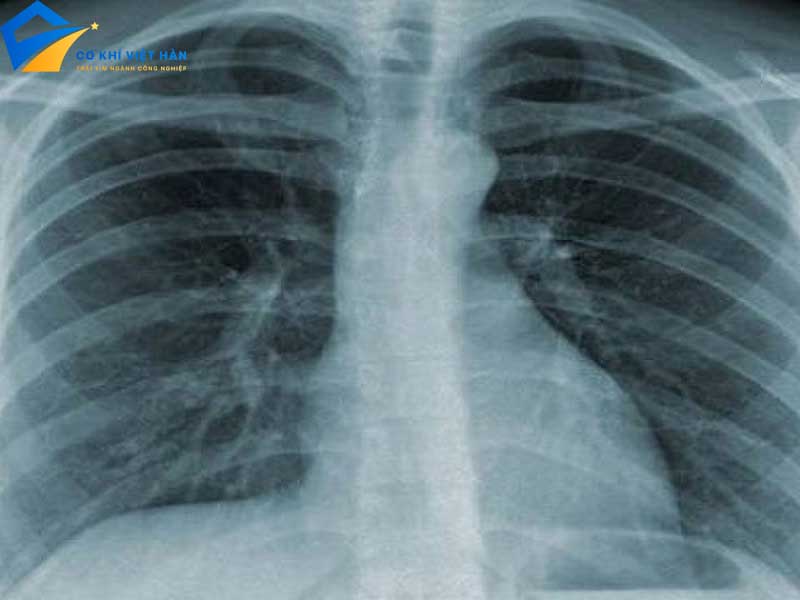

Tính xuyên thấu: Tia X có khả năng xuyên qua các vật liệu khác nhau, từ xương cho đến mô mềm, điều này làm cho chúng trở thành công cụ quan trọng trong chẩn đoán hình ảnh.

Tác dụng lên phim ảnh: Khi tia X chiếu vào phim chụp, chúng tạo ra hình ảnh rõ nét, giúp bác sĩ xác định tình trạng sức khỏe của bệnh nhân.

Trong Y học: Tia X được sử dụng rộng rãi trong y học với những ứng dụng chính như:

- Chụp X-quang: Là phương pháp chẩn đoán hình ảnh phổ biến nhất, giúp xác định tình trạng xương, mô và các cơ quan nội tạng.

- Các kỹ thuật hình ảnh khác: Bao gồm CT scan và MRI, giúp cung cấp hình ảnh chi tiết hơn về cấu trúc bên trong cơ thể.